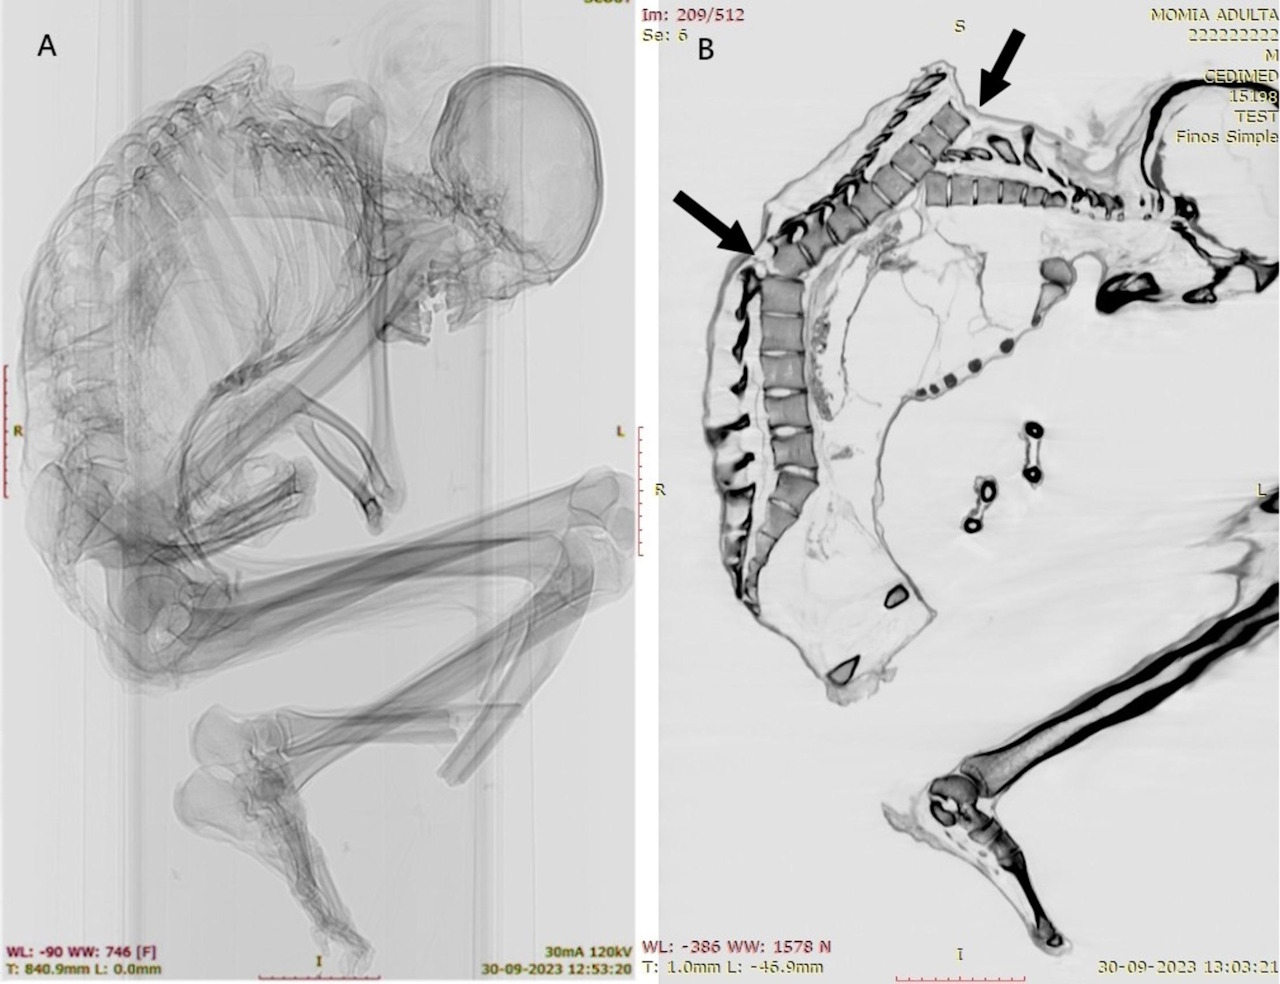

Рентгенівський знімок і комп'ютерна томографія решток, на яких видно травми хребта чоловіка. Morales & Garrido / International Journal of Osteoarchaeology, 2025

У померлого виявили зміщення хребта в районі четвертого та п’ятого грудних хребців, множинні травми ребер, переломи ключиць і лопаток, перелом 12-го грудного хребця, косий перелом великогомілкової кістки лівої ноги та інші травми нижніх кінцівок, пов’язані з великим тиском на них. Ці ушкодження вказали науковцям на те, що чоловік пережив удар важкого предмета, який припав на верхню ліву частину його спини. Такі травми характерні для жертв зсувів ґрунту чи обвалів у шахтах.